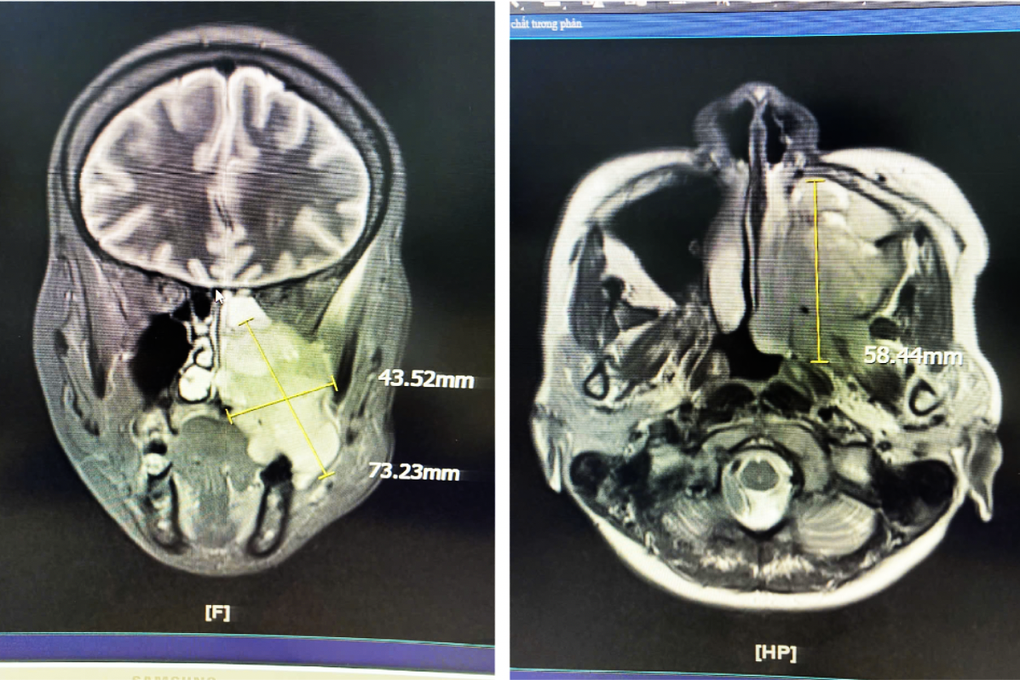

Các chẩn đoán hình ảnh bằng MRI, nội soi tai mũi họng cho thấy, chị S. có khối u xuất phát từ xoang hàm – sàng trái, lan xuống khẩu cái, hố chân bướm hàm và vùng dưới thái dương trái.

Khối u với kích thước lớn có thể nhận thấy dễ dàng trên phim chụp cộng hưởng từ MRI (Ảnh: BVCC).